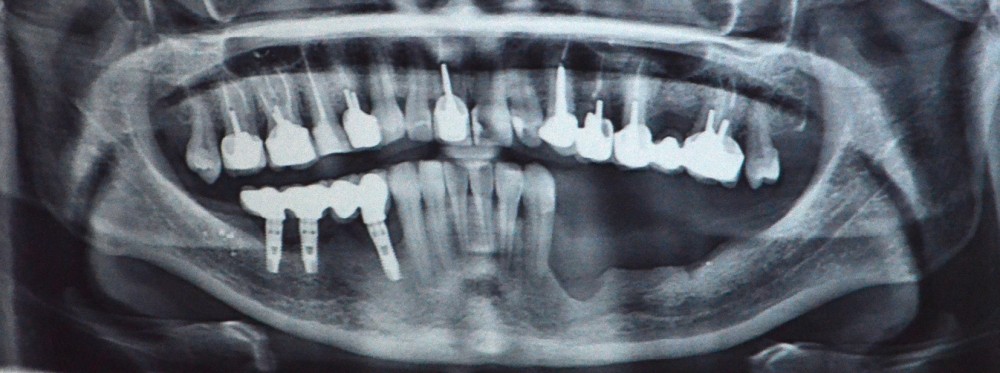

Il s’agit d’une jeune patiente 38 ans ayant présenté une perte osseuse à la suite de péri-implantite. Les implants ont été déposés. La patiente présente une atrophie mandibulaire postérieure classée Cawood V (fig. 1).